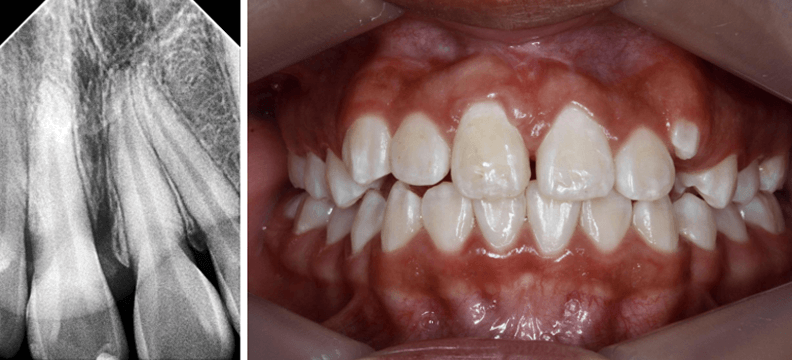

Paciente de 10 años de edad, sexo femenino, acude a consulta para evaluación ortodóntica durante un tratamiento de ortodoncia iniciado en otra consulta, en antecedentes patológicos previos refiere extracción de odontoma compuesto en sector antero-superior del cuadrante 1. Se realiza registro fotográfico (Fig 1) donde se observa presencia de una inserción papilar del frenillo labial, ausencia clínica del incisivo central 1.1 junto con escaneo intraoral en donde se evidencia el estado del tratamiento ortodóntico (Fig 2, 3, 4)

Fig 1-4. Fotografía intraoral de frente y capturas de pantalla de escaneo intraoral vista oclusal, lateral derecha e izquierda

El plan de tratamiento consistió en retirar la ortodoncia fija anterior y cementar brackets con técnica 4x2 filosofía Roth 0,022 con una secuencia de arcos 0.014 niti termoactivado, 0.018niti termoactivado previo a procedimiento quirúrgico. Se requieren 8 mm (espacio requerido) para el incisivo central 1.1 y se tenía un espacio inicial de 6,09 (espacio disponible) (Fig 9 y 10), para control radiográfico inicial se realizó una radiografía periapical con técnica de bisectriz (Fig 11)

Fig 9 y 10. Espacio disponible y espacio requerido

Fig 11. Rx periapical con técnica de bisectriz